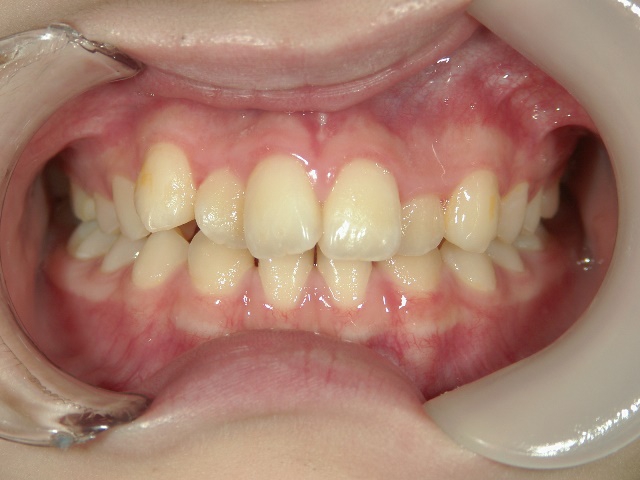

舌側プチワイヤー矯正/上顎のみ 症例(2)

13歳 女性 袋井市在住 治療期間 1年

矯正歯科 治療後 正面